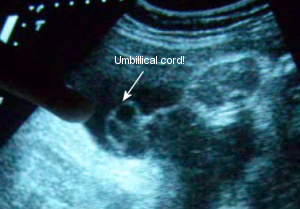

Sono Pic: